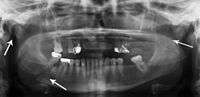

Panoramic radiography

Panoramic radiographs are tomograms where the mandible is in the focal trough and show a flat image of the mandible. Because the curve of the mandible appears in a 2-dimensional image, fractures are easier to spot leading to an accuracy similar to CT except in the condyle region. In addition, broken, missing or malaligned teeth can often be appreciated on a panoramic image which is frequently lost in plain films. Medial/lateral displacement of the fracture segments and especially the condyle are difficult to gauge so the view is sometimes augmented with plain film radiography or computed tomography for more complex mandible fractures.

Research has shown that panoramic radiography is similar to computed tomography in its diagnostic accuracy for mandible fractures and both are more accurate than plain film radiograph.[11] The indications to use CT for mandible fracture vary by region, but it does not seem to add to diagnosis or treatment planning except for comminuted or avulsive type fractures,[12] although, there is better clinician agreement on the location and absence of fractures with CT compared to panoramic radiography.[13]

multiple mandible fractures of a patient in the right condyle (extracapsular/neck/not dislocated), right body (vertically unfavourable) and left coronoid process